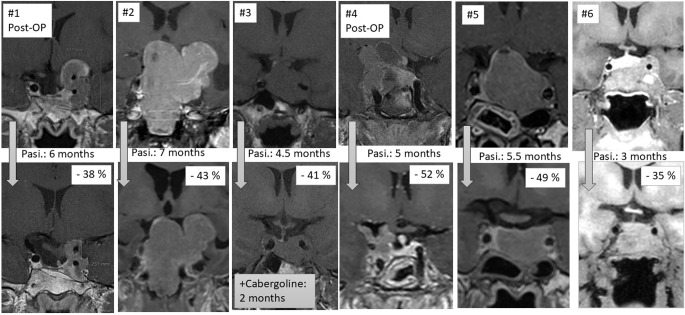

Methods: We present the efficacy of the second-generation SRL, pasireotide, in six patients anticipated to be resistant to first-generation SRLs. The patients had large, hyperintense tumors on T2-weighted MRI and sparse granulation pattern by histology.

Results: Over three to eight months, pasireotide reduced tumour volume in all patients and improved GH and IGF-1 levels. Visual field defects normalised. Despite hyperglycemia, requiring antidiabetic treatment in two patients, pasireotide proved effective as a first pharmacological therapy.